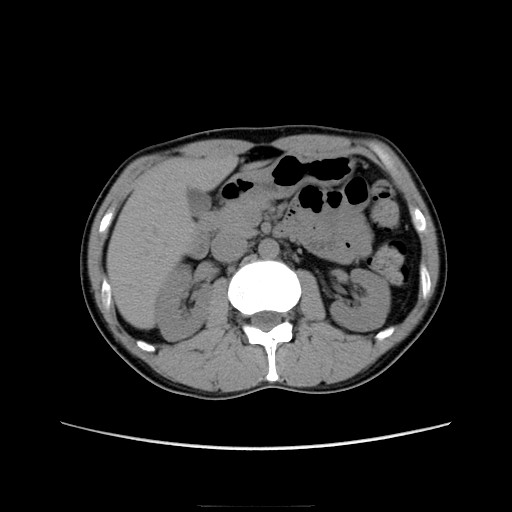

CT画像、腫瘍マーカー共に問題なし。

ではその「3cm」をCTで確認しましょうw。

おへそのあたりの部分です。